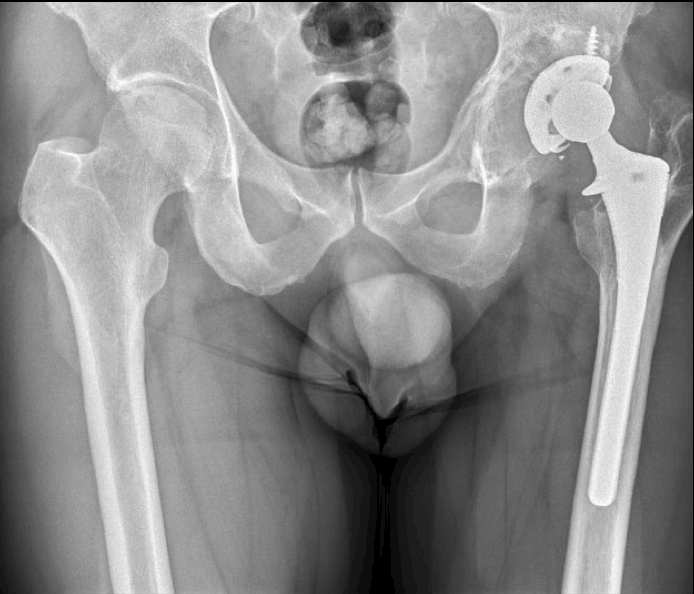

Acetabular replacement, 2015. Last follow-up at the previous center.

First visit to Hospital Parc Taulí (2021):

- Change of treatment center

- No pain. Proper function

- Age: 47 years

October 2022:

- Age: 48 years

- Reports pain

- Follow-up scheduled for 2023.